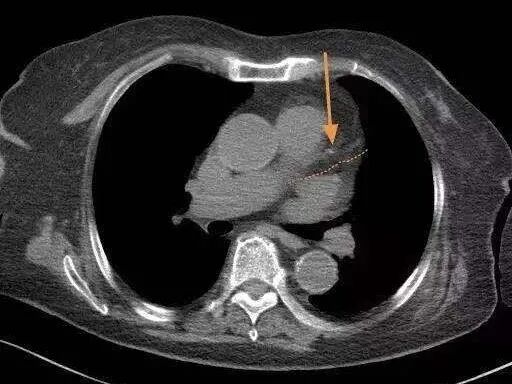

随着年龄增长,很多人会发生冠状动脉硬化,形成一些软硬斑块,引发冠心病。但这位老人只有很小的一点钙化(如图),比很多60岁的人都要好。而且检查发现,老人肺里没有结节,很干净。①

“影像科豪大夫“图